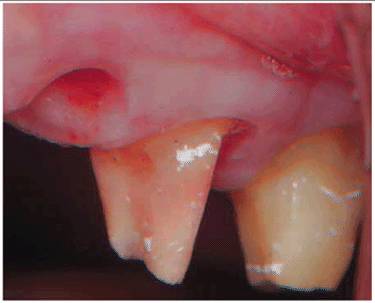

blush on the tooth appears (Figures 19-33A, and 19-33B) during or after preparation, it is

obvious that the 2-mm remaining dentin barrier has been violated. The

probability of complete inflammatory reversibility and healing of a noticeably

hemorrhagic pulp is minimal. Considering that additional procedures are

required to finish the crown, elective endodontics should be instituted before

continuing. If, at any time, a patient elects to forego endodontic therapy

Figure 19-33A: Pink crown preparation 1 week following instrumentation.

Figure 19-33B: Hemorrhagic pulp with extravasation of blood. (Photograph courtesy of Dr. Harold R. Stanley.)